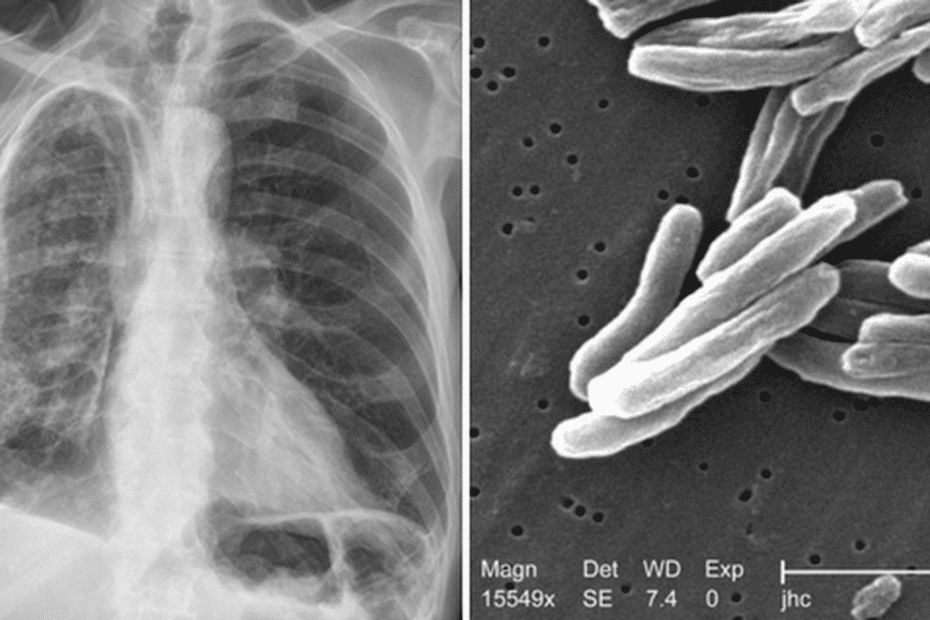

Un cas de tuberculose bovine, causé par Mycobacterium bovis, a été diagnostiqué biologiquement et signalé à l’agence régionale de santé. Cette alerte a été émise par l’hôpital de proximité de Saint-Georges de l’Oyapock.

La tuberculose bovine est une zoonose, c’est-à-dire une infection qui peut être transmise aux humains par les animaux. Les bovins sont considérés comme le réservoir de cette maladie, qui peut également affecter d’autres espèces de mammifères, qu’ils soient domestiques ou sauvages. La tuberculose bovine présente des symptômes similaires à ceux de la tuberculose pulmonaire chez l’homme.

Dans ce cas particulier, la personne porteuse de la tuberculose a été accueillie par l’hôpital de Saint-Georges en mai 2024. Il s’agit d’une patiente brésilienne vivant avec le virus d’immunodéficience humaine (VIH). Les bactéries responsables de la tuberculose humaine, comme Mycobacterium bovis, sont souvent considérées comme des germes opportunistes. Cela signifie qu’elles infectent plus facilement les personnes ayant une immunité fragile, ce qui semble être le cas pour cette patiente.

Les individus concernés par cette maladie sont le plus souvent infectés par l’ingestion de produits laitiers non pasteurisés provenant d’animaux infectés, mais également par inhalation d’aérosols contaminés ou par contact direct via des plaies cutanées.

Le moyen de transmission le plus significatif demeure l’inhalation de postillons infectés. Les symptômes courants de la tuberculose bovine incluent :

Dans les cas où les poumons sont gravement affectés, des quintes de toux intermittentes peuvent également se manifester.